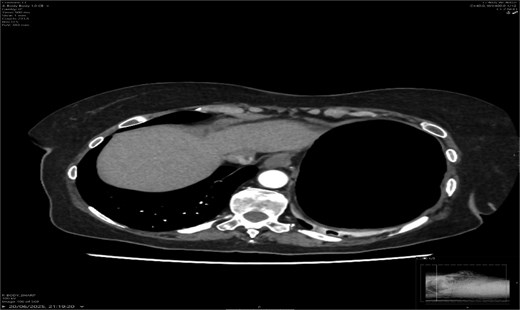

A contrast-enhanced CT scan of the abdomen demonstrated a whirl sign at the mesenteric root (Figs 1 and 2), dilated transverse colon with a transition point at the splenic flexure (Fig. 3), and no evidence of ischemia or perforation (Fig. 4). These findings were consistent with TCV.

Axial CT showing dilated transverse colon at the splenic flexure.